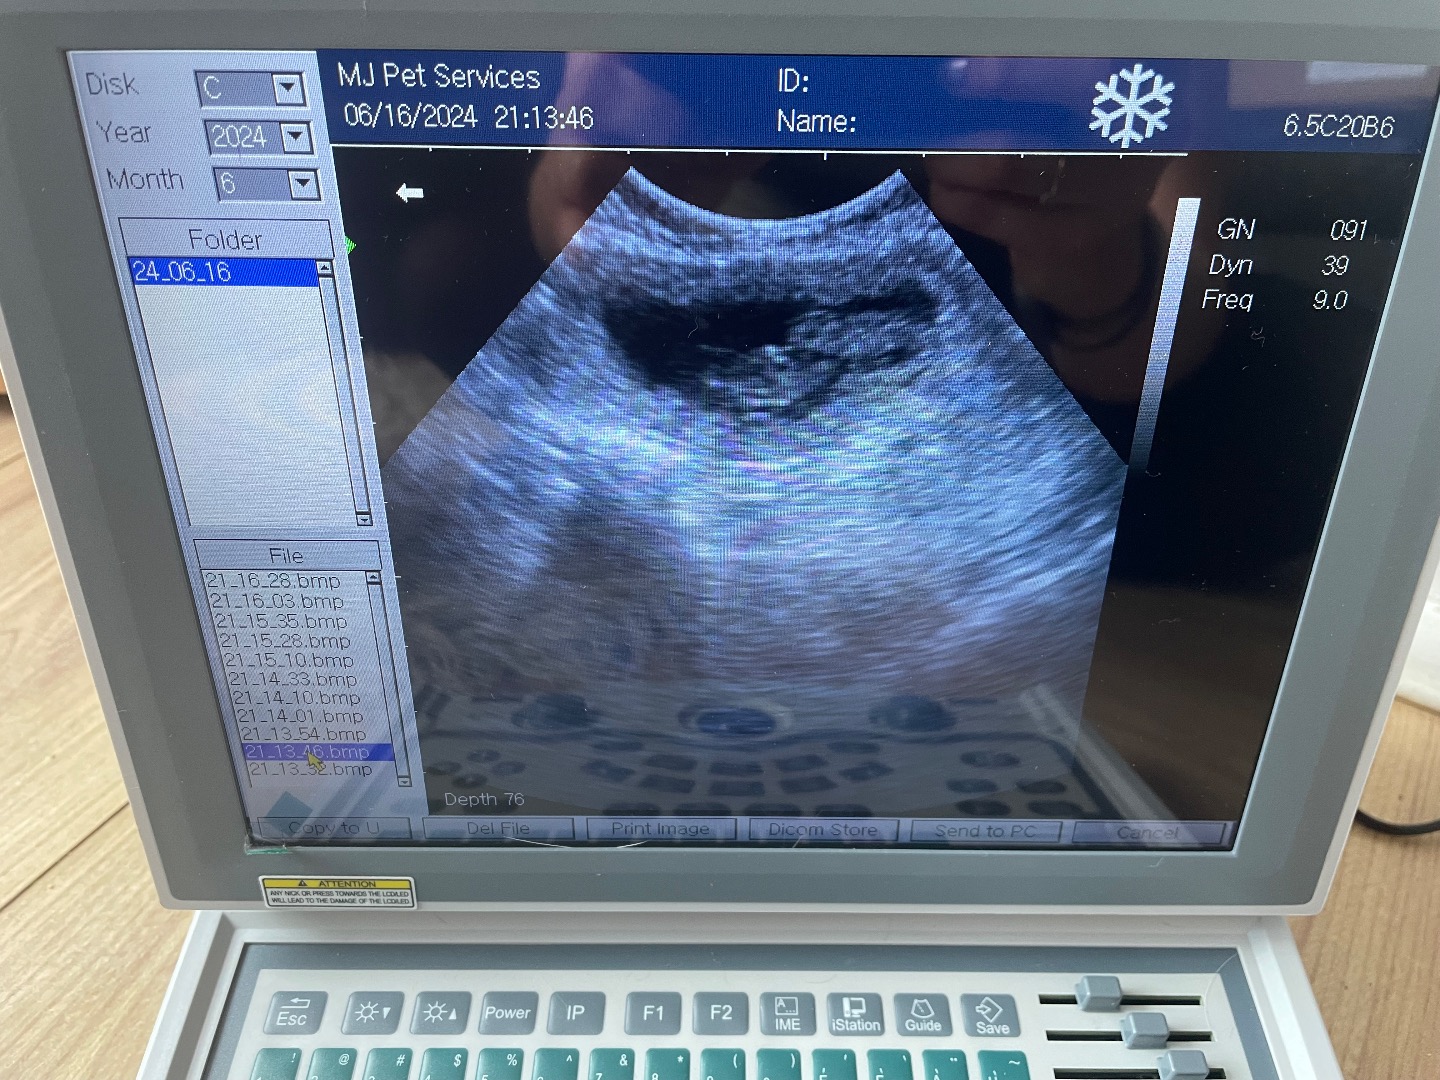

Mini Poodle scan

Urgent vet referral scan, no pups, lots of fluid, dog ended up have emergency operation